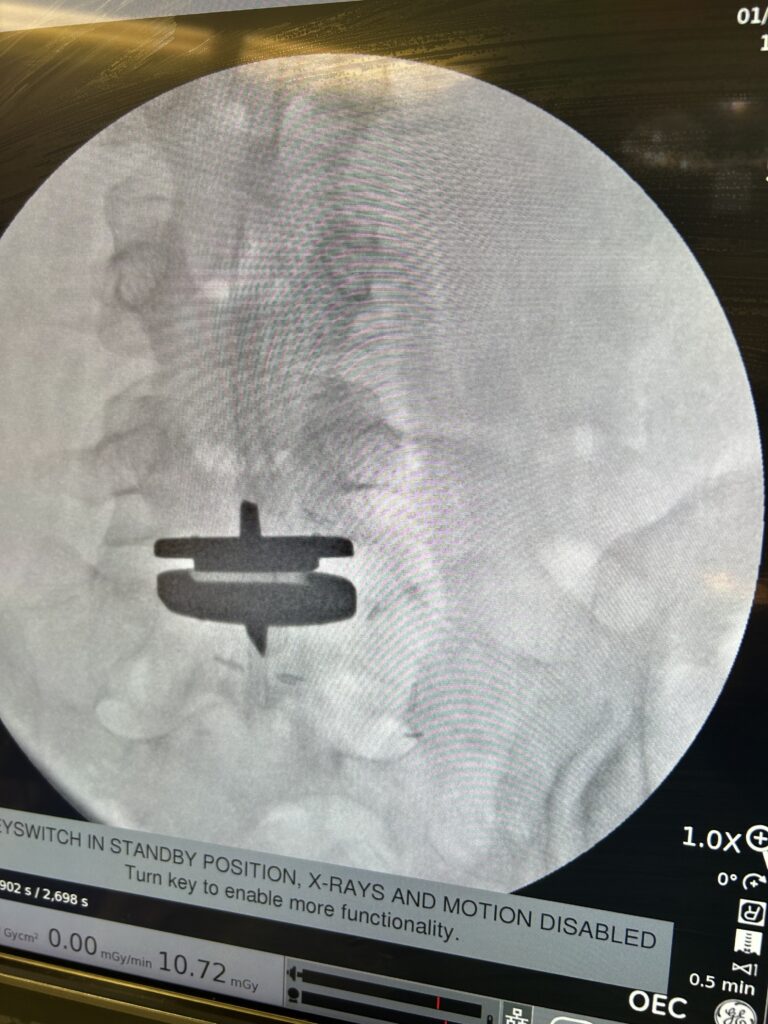

Dr. Daniel Choi recently performed a lumbar total disc replacement at St. Francis Hospital, reflecting an important professional milestone and the continued expansion of advanced spine surgery options on Long Island. Dr. Choi is one of few spine surgeons on Long Island offering lumbar disc replacement, a highly specialized procedure designed to preserve motion in the lower spine.

The procedure uses the prodisc® L Total Disc Replacement system from Centinel Spine, one of the most studied lumbar disc replacement technologies in the world. Backed by decades of clinical research, the prodisc® L system is designed to restore disc height, maintain motion, and accommodate a patient’s individual lumbar anatomy.